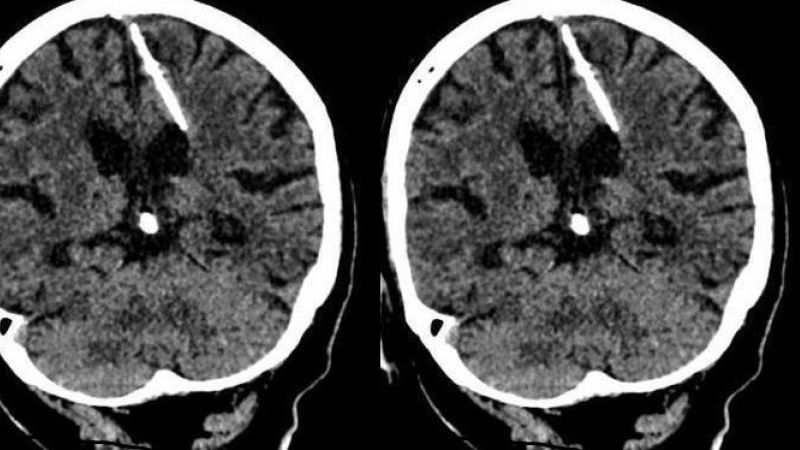

اكتشف اطباء روس بالصدفة ابرة طولها ثلاثة سنتمترات موجودة منذ ثمانين عاما داخل دماغ امرأة مسنة اثناء قيامهم باجراء فحص لها بالتصوير المقطعي.

وأضافت أن الفحوص اظهرت ان المراة تعيش مع الابرة البالغ طولها ثلاثة سنتمترات داخل دماغها "منذ ولادتها" ما يؤكد ان والديها كانا قررا التخلص منها، لكن محاولتهما لم تفلح.

وقرر الاطباء عدم استخراج الابرة تفاديا لتعريض المراة الى مضاعفات، بحسب ادارة الصحة المحلية.

واوضحت الادارة ان الفحص اظهر ان الابرة اخترقت الفص الجداري الأيسر لدماغ المراة، لكنها كتبت لها النجاة حيث لم يتسبب ذلك في وفاتها كما كان يأمل والداها.